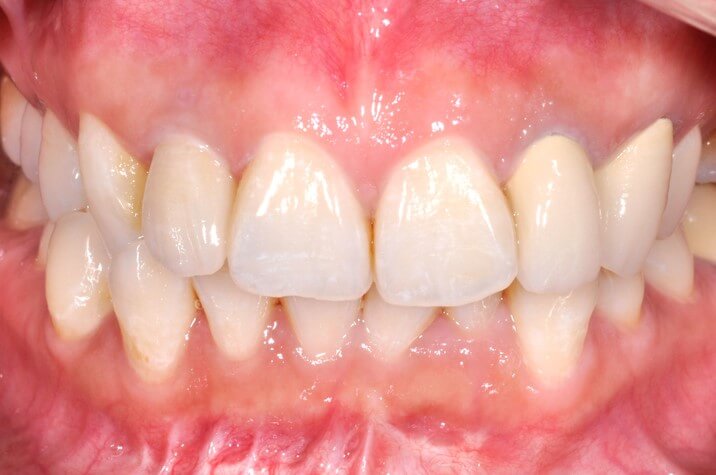

模仿自然牙齒的全瓷假牙安裝

安裝後側面

正面